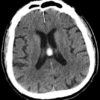

Nang keo não thất

Nang keo não thất - Ảnh 4

» Thông tin: Nữ giới – 70 tuổi.

» Lâm sàng: Đau đầu.